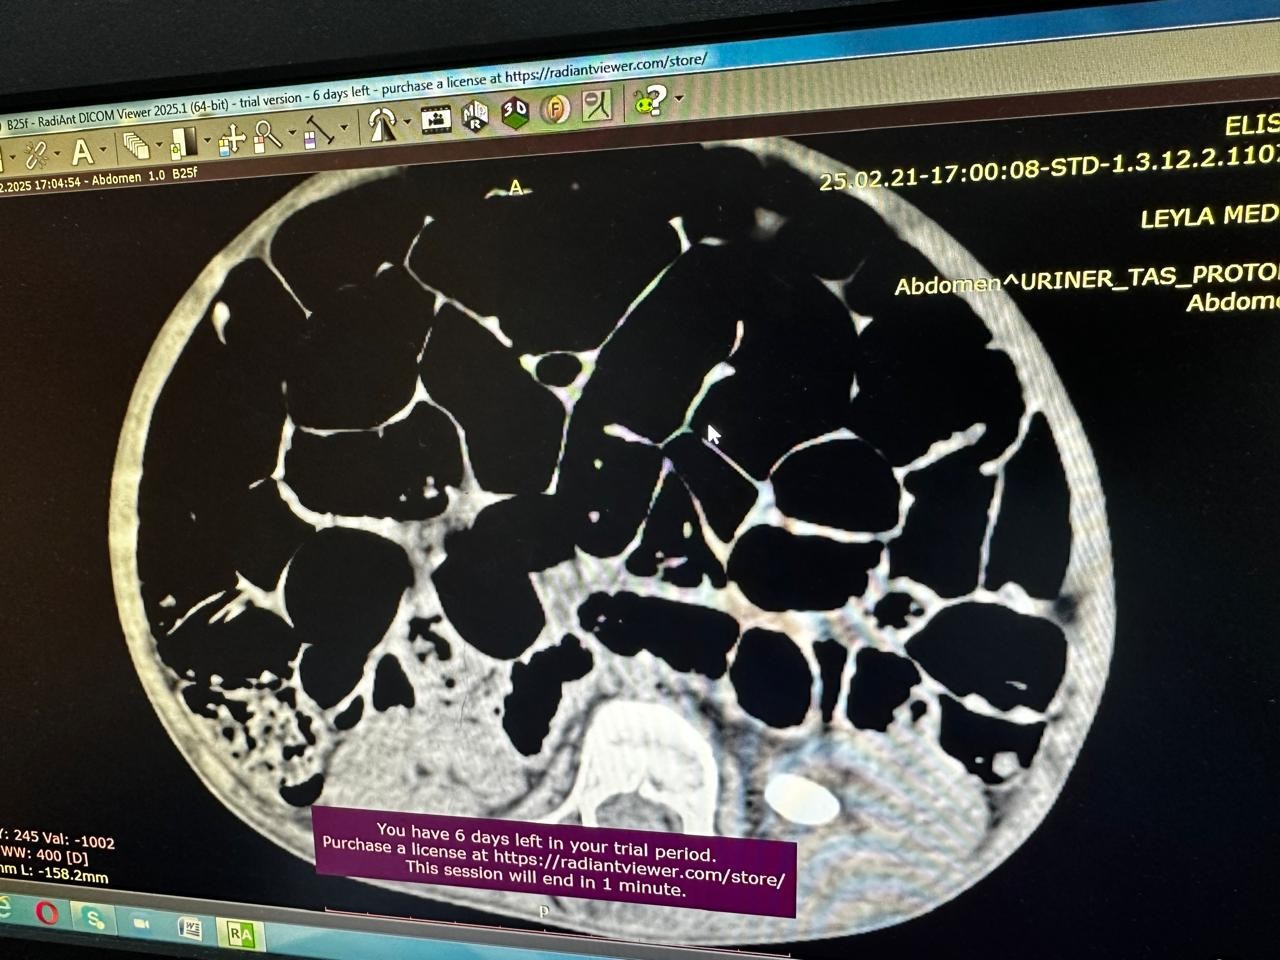

Əməliyyat zamanı xəstənin sol böyrəyindən mərcanvari daş xaric edilib.